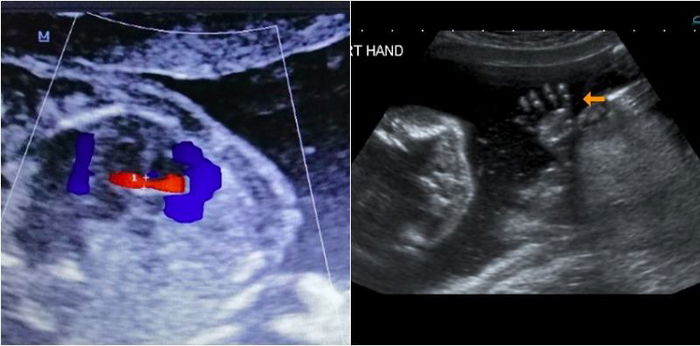

- Tangan dan kaki – setiap tulang termasuk jari jemari.

Kecacatan tangan dan kaki serius | Ketiadaan tulang tangan atau kaki atau bentuk tulang yang bengkok dan sangat pendek | 90% |